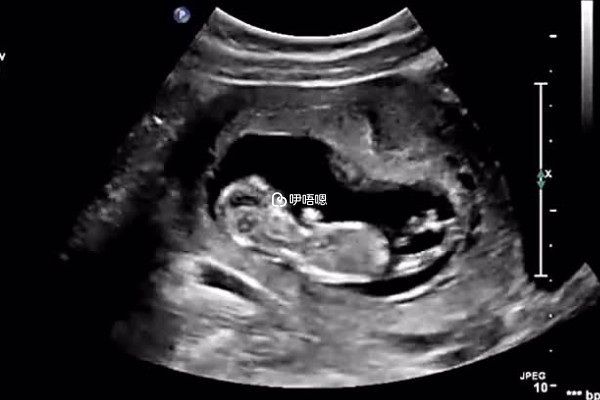

NT是檢查胎兒頸部後面透明帶,也叫早期唐篩,正常妊娠第10到14周頸項透明層厚度隨孕周略微上升,檢測值小於2.5毫米時判為正常,可以早期診斷染色體疾病和早期發現多種原因造成的胎兒異常,目前通過nt值看胎兒性別是不準的,以下則是網上傳言的nt值看男孩女孩的方法: